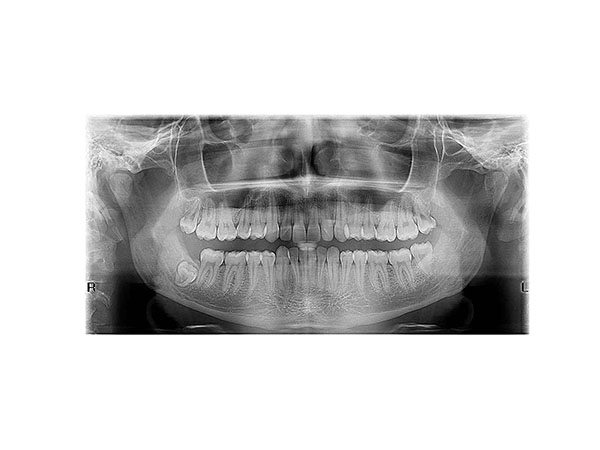

We perform all types of dental, jaw, sinus, and cervical vertebrae imaging, with the following three types being the most requested:

• Orthopantomogram (digital panoramic X-ray of the entire jaw)